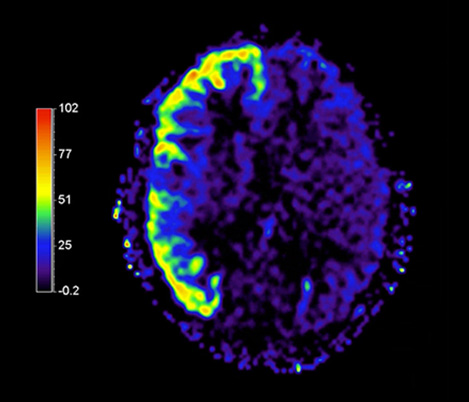

Sang noir

Hôpital Erasme, Belgique

Imagerie du sang noir par IRM des patients atteints du VIH avec vascularite cérébrale

L’imagerie du sang noir a été utile pour suggérer le diagnostic et choisir le traitement.